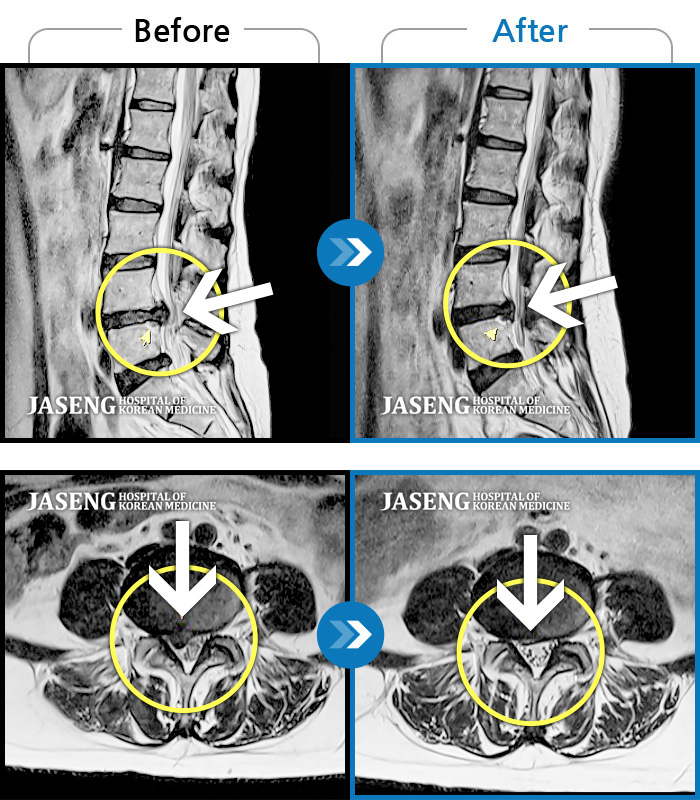

허리디스크

광주 · 김동은 원장

좌측 골반 및 종아리부터 발까지 이어지는 저림과 통증으로 내원하셨습니다.

촬영시기

2023.10.03 ~ 2025.08.14

2025.08.22